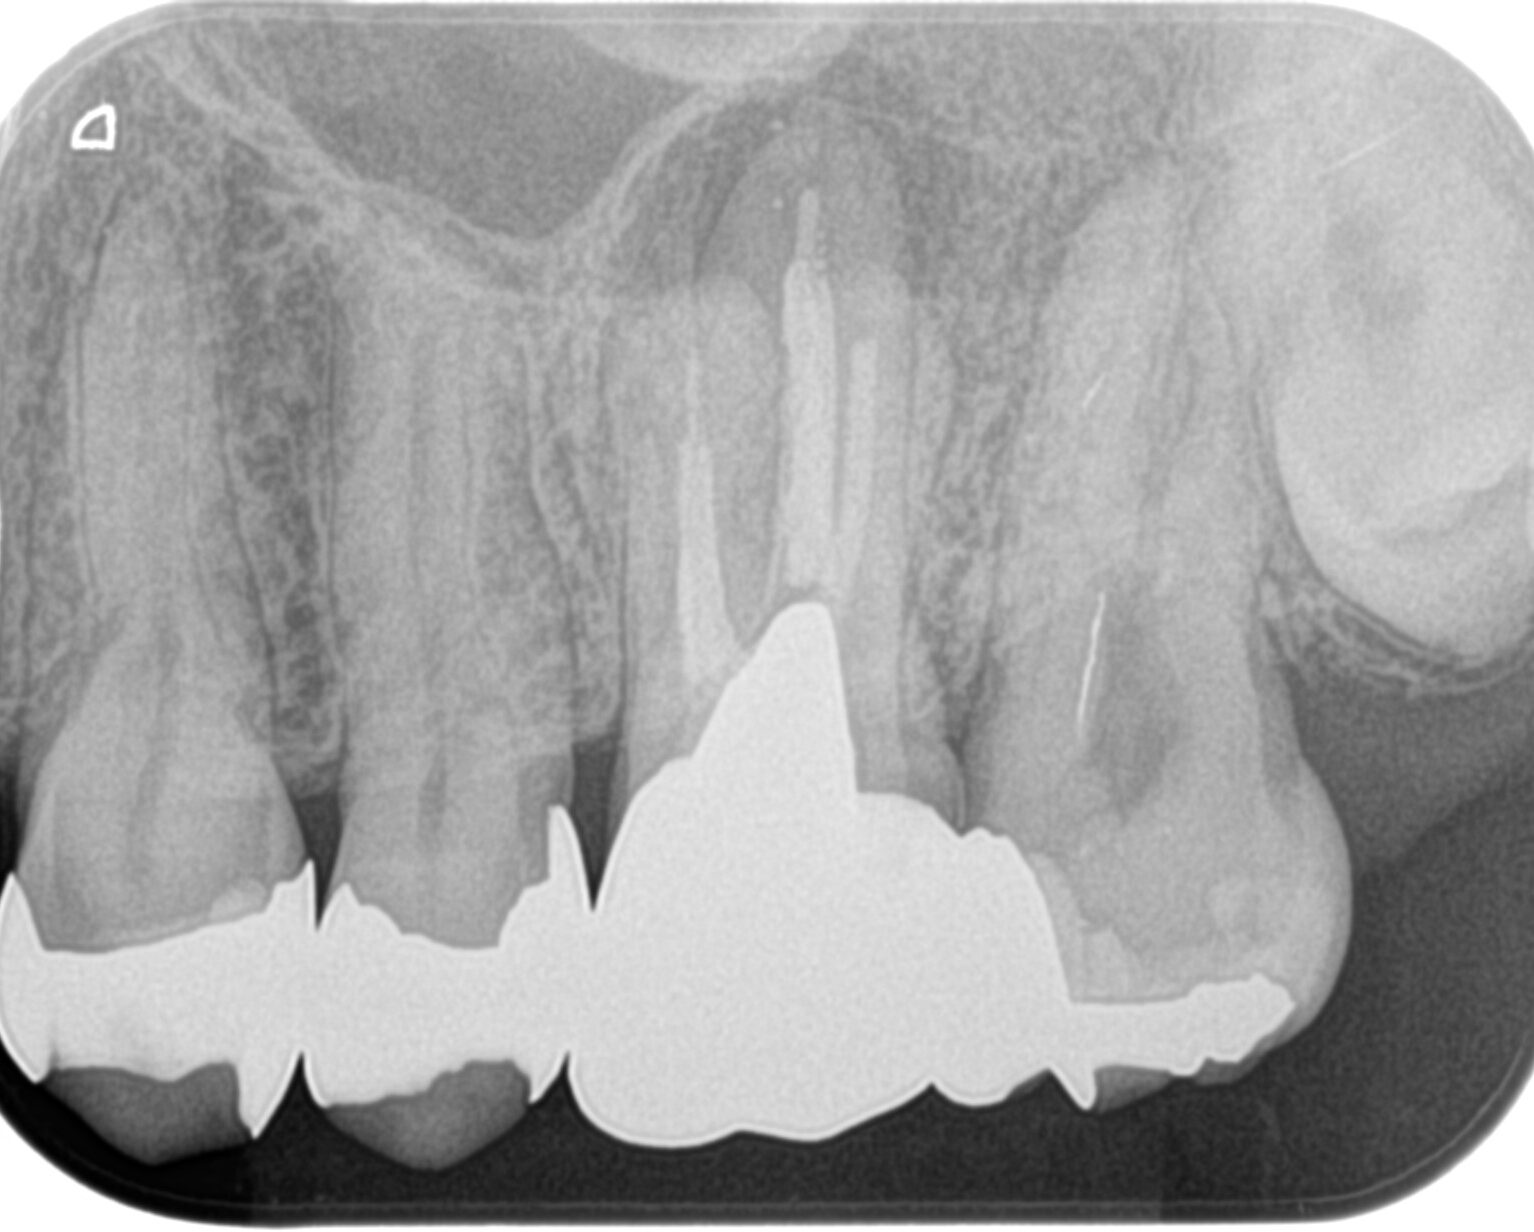

#14 Re-RCT(2023.6.20)

MB,DB,Pの3根全てに病変がある。

再根管治療を行うが、

DB以外はほぼ形成ができない状態であった。